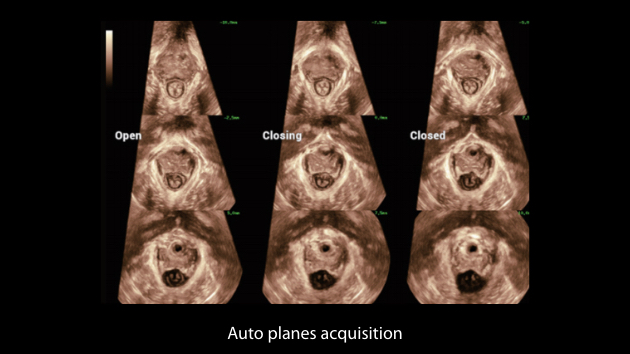

Nuewa I9 Elite Edition ├© progettato appositamente per l'assistenza sanitaria a donne e neonati e offre un'esperienza innovativa sviluppata sulla base di conoscenze approfondite relative a scenari clinici complessi, per risposte accurate e tempestive, nonch├® un'efficienza e un'esperienza utente eccezionali